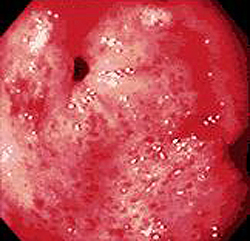

- Эзофагогастродуоденоскопия. Осмотр слизистой при ЭГДС выявляет патогномоничные морфологические признаки заболевания. Для гастрита характерны отечность, гиперемия, эрозии, истончение и атрофия эпителия, участки метаплазии, усиление сосудистого рисунка.

- ФГДС. Эндоскопическая картина дает представление о локализации воспаления, его выраженности и глубине. Для уточнения диагноза и исключения малигнизации берут биопсию слизистой из различных отделов желудка. Определяют уровень кислотности желудочного сока (pH-метрия).